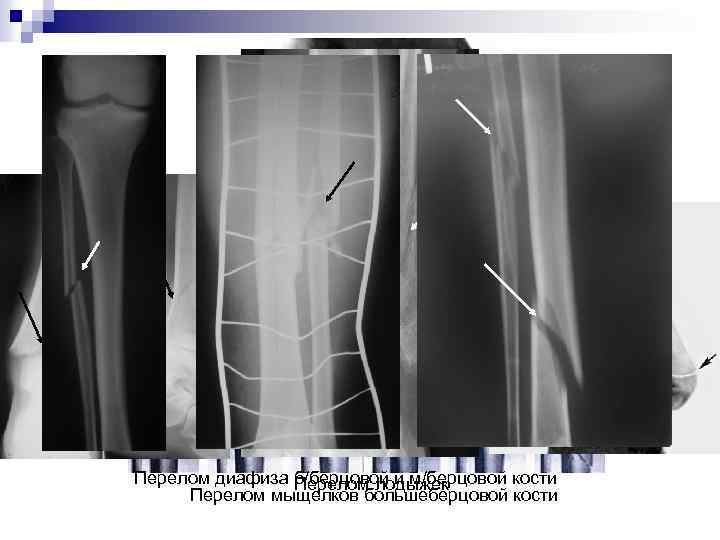

Переломы голени Причины повреждения: сильный удар по голени, падение тяжелых предметов на ногу, резкое вращение голени при фиксированной стопе. Делятся на: n Переломы верхнего отдела (мыщелков б/берцовой кости, бугристости б/берцовой кости, переломы головки и шейки м/берцовой кости) n Переломы средней части костей голени – диафиза м/берцовой или б/берцовой кости n Переломы обоих диафизов костей голени и переломы нижнего отдела голени – области голеностопного сустава.

Перелом диафиза б/берцовой и м/берцовой кости Перелом лодыжек Перелом мыщелков большеберцовой кости